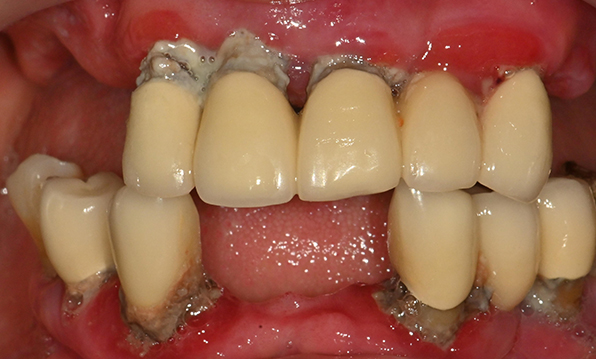

전체 임플란트가 필요한 경우

치아가 얼마 남아있지 않은 경우

치주질환이 심해, 치아가 있더라도 제 기능을 하지 못하는 경우

틀니 사용이 불편한 경우

전체 임플란트를 해야하는 환자들은

대부분 고령의 환자들로 오랜 틀니 사용

또는 노화로 인해 치조골이

거의 남아있지 않는 경우가 많습니다.

이 때, 치조골 이식을 병행하여 잇몸뼈 재건 후 안정적인 임플란트 식립을 하고 있습니다.

치료기간 : 2021.04.12~2021.09.15